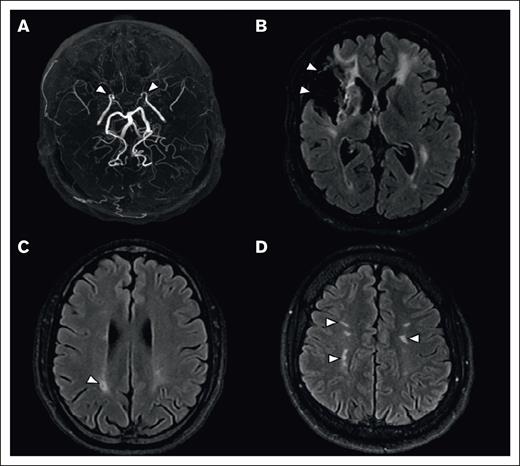

An intracranial vasculopathy was identified in 47 (49%; 95% CI, 39-59) patients, associated with Moya-Moya syndrome in 29 (30%; 95% CI, 21-39) patients. Additionally, 17 (18%; 95% CI, 10-26) patients had an extracranial vasculopathy, which was isolated in 6 patients. Overall, the prevalence of vasculopathy (intra and/or extracranial) was 55% (95% CI, 45-65; n = 53). MRI findings are summarized in Figure 1.

Brain MRI of lesions associated with SCD. (A) Maximal intensity projection reconstruction of a 3D-TOF MRA, showing occlusion of the distal segment of internal carotid arteries (arrowheads). (B-D) Axial 2-dimensional fluid attenuated inversion recovery (2D FLAIR), showing a territorial infarct (B, arrowheads), an isolated lacune (C, arrowhead), and white matter hyperintensities of presumed vascular origin (D, arrowheads).